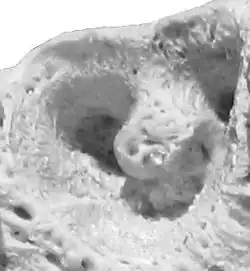

Zębodół – występujące u ssaków i niektórych gatunków gadów zagłębienie w szczęce i żuchwie. Znajdują się w nich korzenie zębów. Ogniwa pierwotne chorych ludzkich zębodołów wykazują większy potencjał wzrostu, u wszystkich występują także cechy osteoblastów[1].